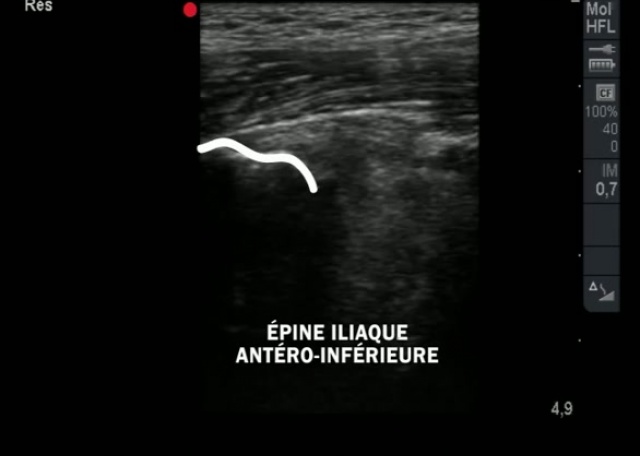

Comment Realiser Un Examen Echographique De La Hanche Youtube

Echographie De La Hanche Video

Debuter En Echo Anatomie De Hanche Hors Nourrisson